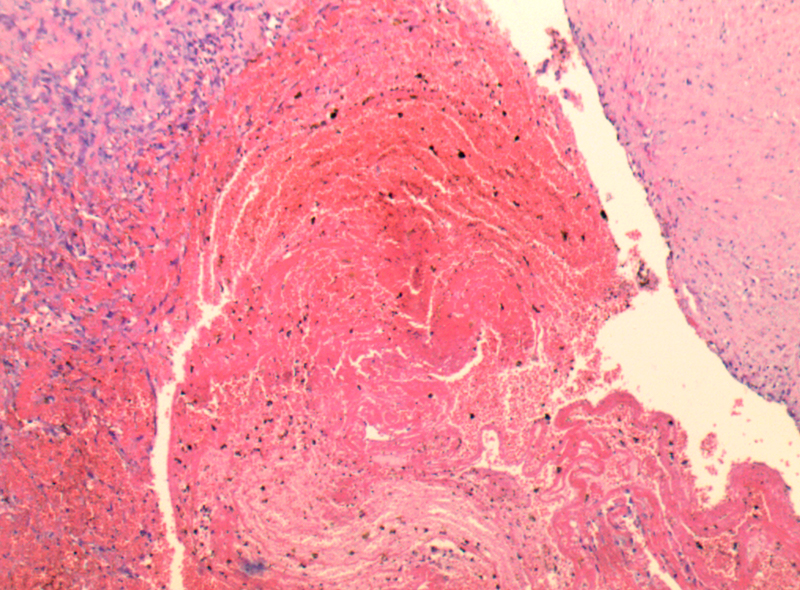

靜脈血栓